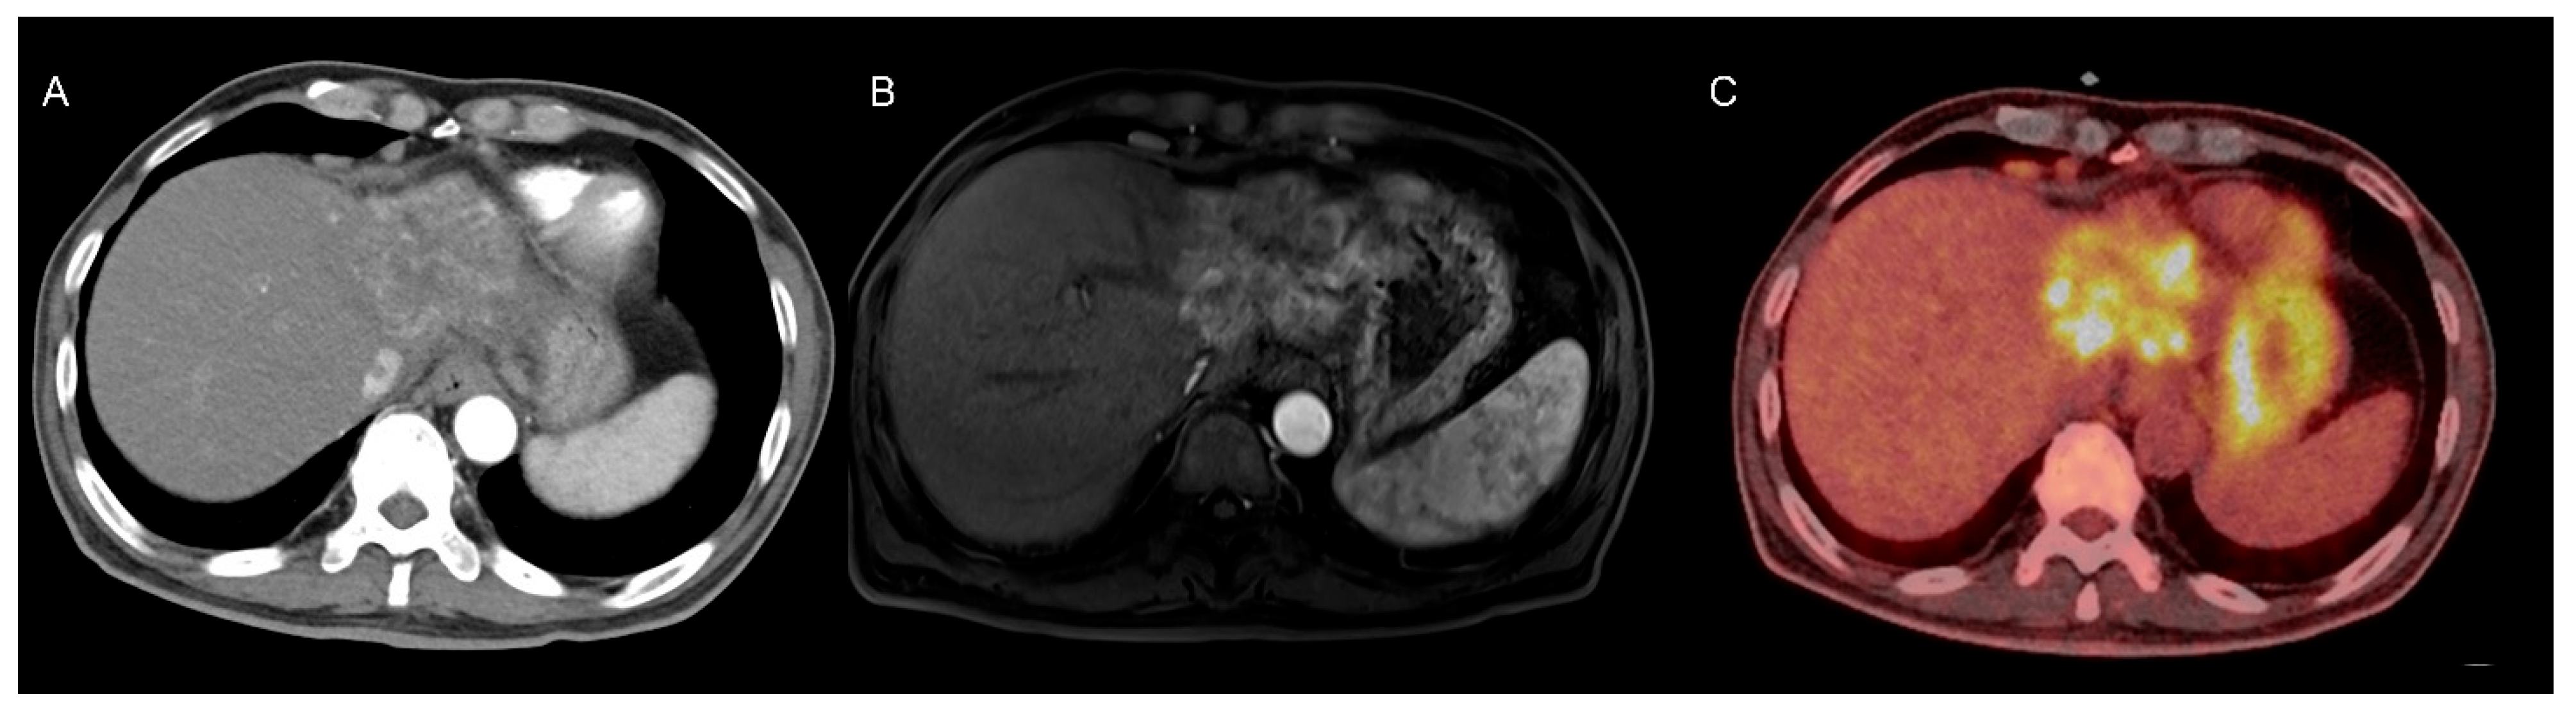

A liver dynamic CT scan revealed a 6.2 cm × 6.1 cm × 4.8 cm heterogeneously enhancing mass in the left lateral section of the liver, along with multiple enlarged lymph nodes in the right pericardiophrenic and porta hepatis areas (Figure 1A). Gadoxetic-acid-enhanced liver MRI showed a 7.8 cm hyperenhancing mass in the left lateral section during the arterial phase of dynamic imaging (Figure 1B). Based on the radiological findings and elevated tumor marker levels, the patient was diagnosed with HCC, modified Union for International Cancer Control (mUICC) stage IVA.

Treatment with atezolizumab bevacizumab was initiated, along with antiviral treatment using tenofovir alafenamide to ensure virologic suppression of the hepatitis B virus. However, follow-up liver MRI after two cycles revealed tumor progression, with the lesion increasing from 7.8 cm to 8.8 cm in its longest axis. A multidisciplinary consultation was conducted, and surgical resection was recommended as the next treatment modality given the progression despite atezolizumab bevacizumab therapy. Preoperative positron emission tomography–computed tomography revealed intense heterogeneous fluorodeoxyglucose uptake within the tumor (Figure 1C). The patient subsequently underwent extended left hepatectomy.

Figure 1. Multimodal Imaging of the Tumorous Lesion. (A) Computed tomography showing heterogeneous arterial enhancement within the lesion. (B) Gadoxetic-acid-enhanced liver magnetic resonance imaging of arterial phase demonstrating heterogeneous enhancement of the lesion. (C) Positron emission tomography–computed tomography of the liver demonstrating intense fluorodeoxyglucose uptake within the lesion.